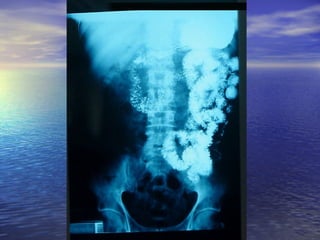

5.- FÍSTULAS: Enf. De Crohn, tumores5.- FÍSTULAS: Enf. De Crohn, tumores

malignos y postoperatoriosmalignos y postoperatorios

6.- ANORMALIDADES EXTRÍNSECAS:6.- ANORMALIDADES EXTRÍNSECAS:

Metástasis , serosa, ascitis, lesionesMetástasis , serosa, ascitis, lesiones

inflamatorias o neoplasias cercanas.inflamatorias o neoplasias cercanas.

7.- DILUCIÓN DEL MEDIO DE7.- DILUCIÓN DEL MEDIO DE

CONTRASTE: Lesiones proximales uCONTRASTE: Lesiones proximales u

obstructivas, Sx. De Zollinger Ellison.obstructivas, Sx. De Zollinger Ellison.